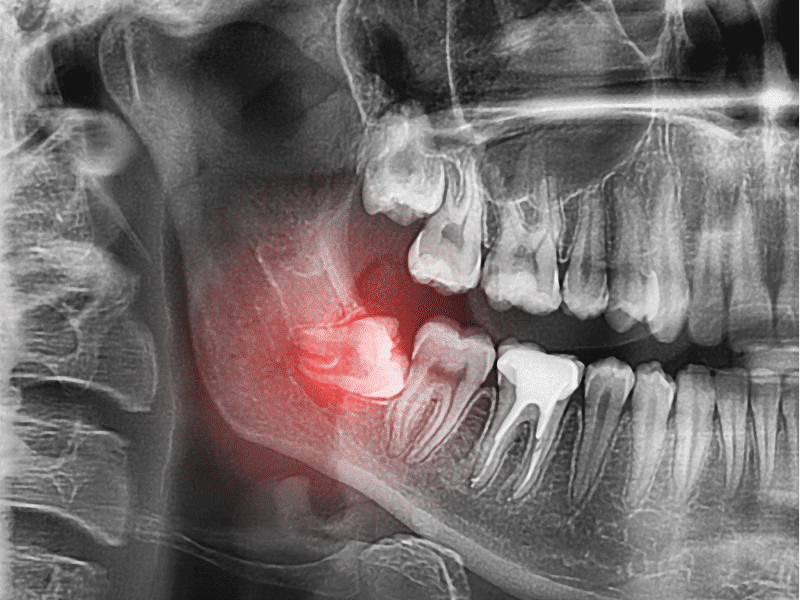

Răng khôn, hay còn gọi là răng số 8, là chiếc răng hàm lớn thứ ba và thường là chiếc răng mọc cuối cùng trong hàm, xuất hiện ở độ tuổi từ 17 đến 25. Mỗi người thường có bốn chiếc răng khôn, bao gồm hai chiếc ở hàm dưới và hai chiếc ở hàm trên.

Các bác sĩ thường khuyên nên nhổ răng khôn trong những trường hợp sau:

- Khi răng khôn mọc lệch hoặc sai vị trí, gây ra các biến chứng như đau nhức, nhiễm trùng và ảnh hưởng không tốt đến các răng bên cạnh.

- Trong trường hợp răng khôn mọc thẳng và có đủ chỗ nhưng hình dạng bất thường gây cản trở, dẫn đến việc thức ăn mắc lại giữa các răng, có thể gây sâu răng hoặc viêm nướu sau một thời gian.

- Nếu răng khôn mọc thẳng, có đủ không gian và không bị cản trở bởi nướu hay xương, nhưng không có răng đối diện để ăn khớp, điều này có thể làm cho răng khôn nhô ra phía hàm đối diện, khiến thức ăn bị nhồi nhét và gây viêm loét nướu ở phía đối diện.